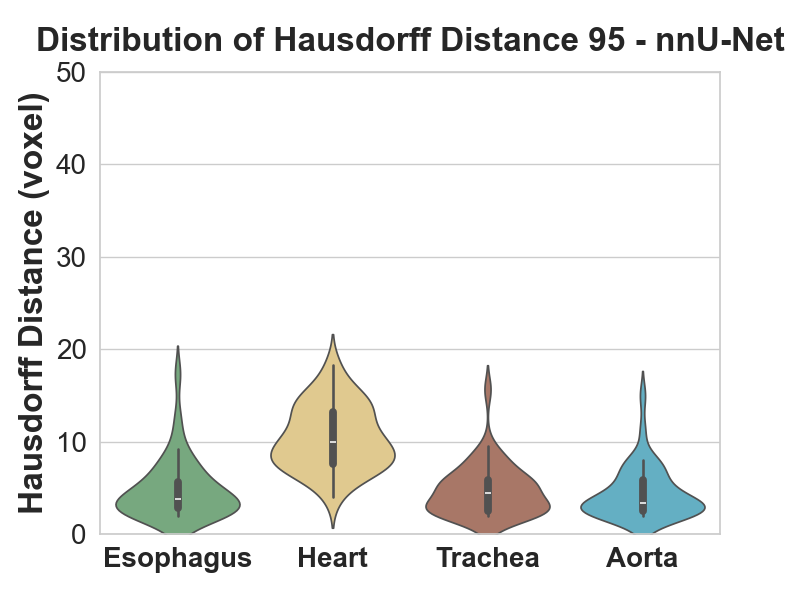

Metrics: Dice coefficient, Hausdorff distance, ASSD (average symmetric surface distance). Hausdorff alone is outlier-prone, so we used both Hausdorff and ASSD together.

- nnU-Net beat both. vs ENet: Dice t(78) = 5.03, p < 0.01; recall t(78) = 5.68, p < 0.01. vs CustomNet: Dice t(78) = 3.42, p < 0.01; recall t(78) = 4.27, p < 0.01.

- The interesting nuance is the heart. Heart Hausdorff actually got worse for CustomNet despite a better Dice, because both CustomNet and nnU-Net over-segment the heart. Heart precision dropped from 0.92 (baseline) to 0.89 (CustomNet), and dropped further on nnU-Net. Recall went up; precision went down. Net Dice still improved but the failure mode is real.

- Where nnU-Net shines is the esophagus. The smallest, hardest organ. Dice distribution shifted up substantially, and both precision and recall improved, where the 2D models struggled most.

3D Full-Resolution nnU-Net is the clear winner for this task: significantly better Dice and recall, smoother predictions (post-processing's connected-component analysis cleans up the artefacts the 2D models leave). The cost is that it over-segments the heart, which would matter for clinical deployment and is the obvious next-step refinement.